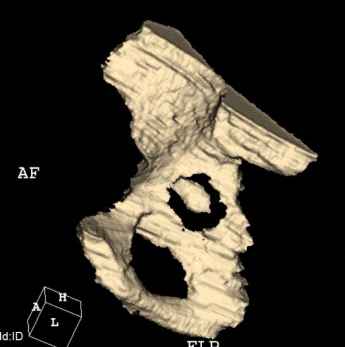

Мужчина, 45 лет. 6 мес. назад перенес тотальное эндопротезирование правого тазобедренного сустава по поводу ложного сустава шейки бедра.

Характер реконструкции вертлужной впадины не известен. Через 3 мес. после операции отметил щелчки и хруст при движениях в области эндопротеза. В анамнезе туберкулез легких. Сейчас, по заключению фтизиатра, в легких активного процесса нет. Местного воспаления нет.Предполагается нестабильность чашки в связи с бактериальным воспалением. Планируется удаление чашки и цемента, пластика дна измельченными аутотрансплантами и гидроксилапатитной керамикой, затем кольцо Мюллер, цементная чашка.

Смущает и ножка - зона просветления вокруг мантии. Предложения по тактике?

прямо скажем, очень загадочная конструкция с проволокой и винтами. :) На основании чего Вы подозреваете септическую нестабильность? Каковы результаты анализов? Согласен с доктором - нужно сделать пункцию. Есть ли снимки до и сразу после операции? Знаете ли Вы диаметр головки,какой будет внутренний диаметр Вашей чашки? Известно ли, чей протез? Может есть смысл найти автора работы и узнать о подробностях установки протеза?